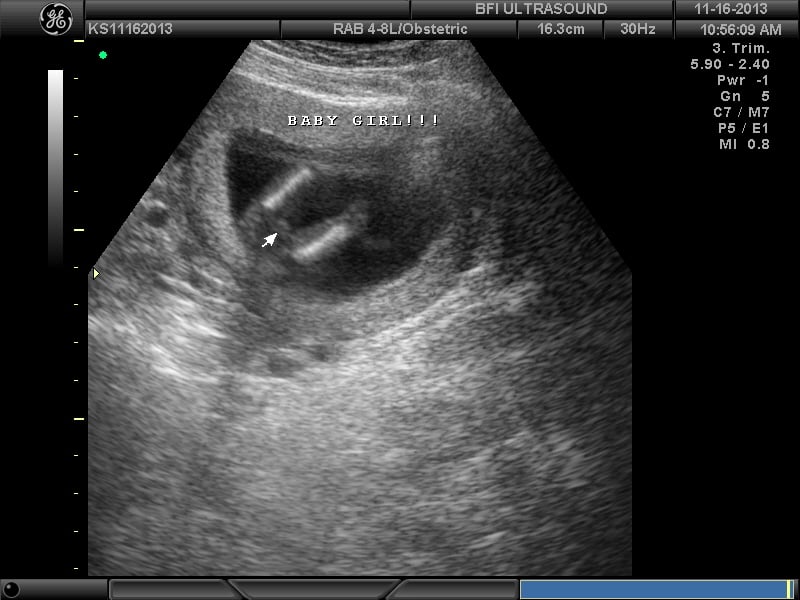

BFP#4 8.27.13 (EDD 5.6.14) DD born 4.23.14